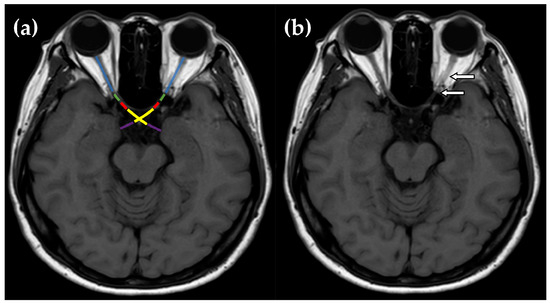

| Segmental enhancement of AVP—no. (%) | ||||||||

| Orbital optic nerve | 40 (52.6) | 15 (37.5) | 17 (70.8) | 8 (66.7) | 0.02 | 0.01 | 0.073 | 0.544 |

| Intracanalicular optic nerve | 10 (13.2) | 2 (5.0) | 4 (16.7) | 4 (33.3) | 0.032 | 0.135 | 0.021 | 0.236 |

| Intracranial optic nerve | 6 (7.9) | 1 (2.5) | 0 (0) | 1 (8.3) | 0.126 | 0.061 | 0.412 | 0.451 |

| Optic chiasm | 0 (0) | 0 (0) | 0 (0) | 0 (0) | - | - | - | - |

| Optic tract | 0 (0) | 0 (0) | 0 (0) | 0 (0) | - | - | - | - |

| ≥2 consecutive segments | 10 (13.2) | 2 (5.0) | 4 (16.7) | 4 (33.3) | 0.032 | 0.135 | 0.021 | 0.236 |